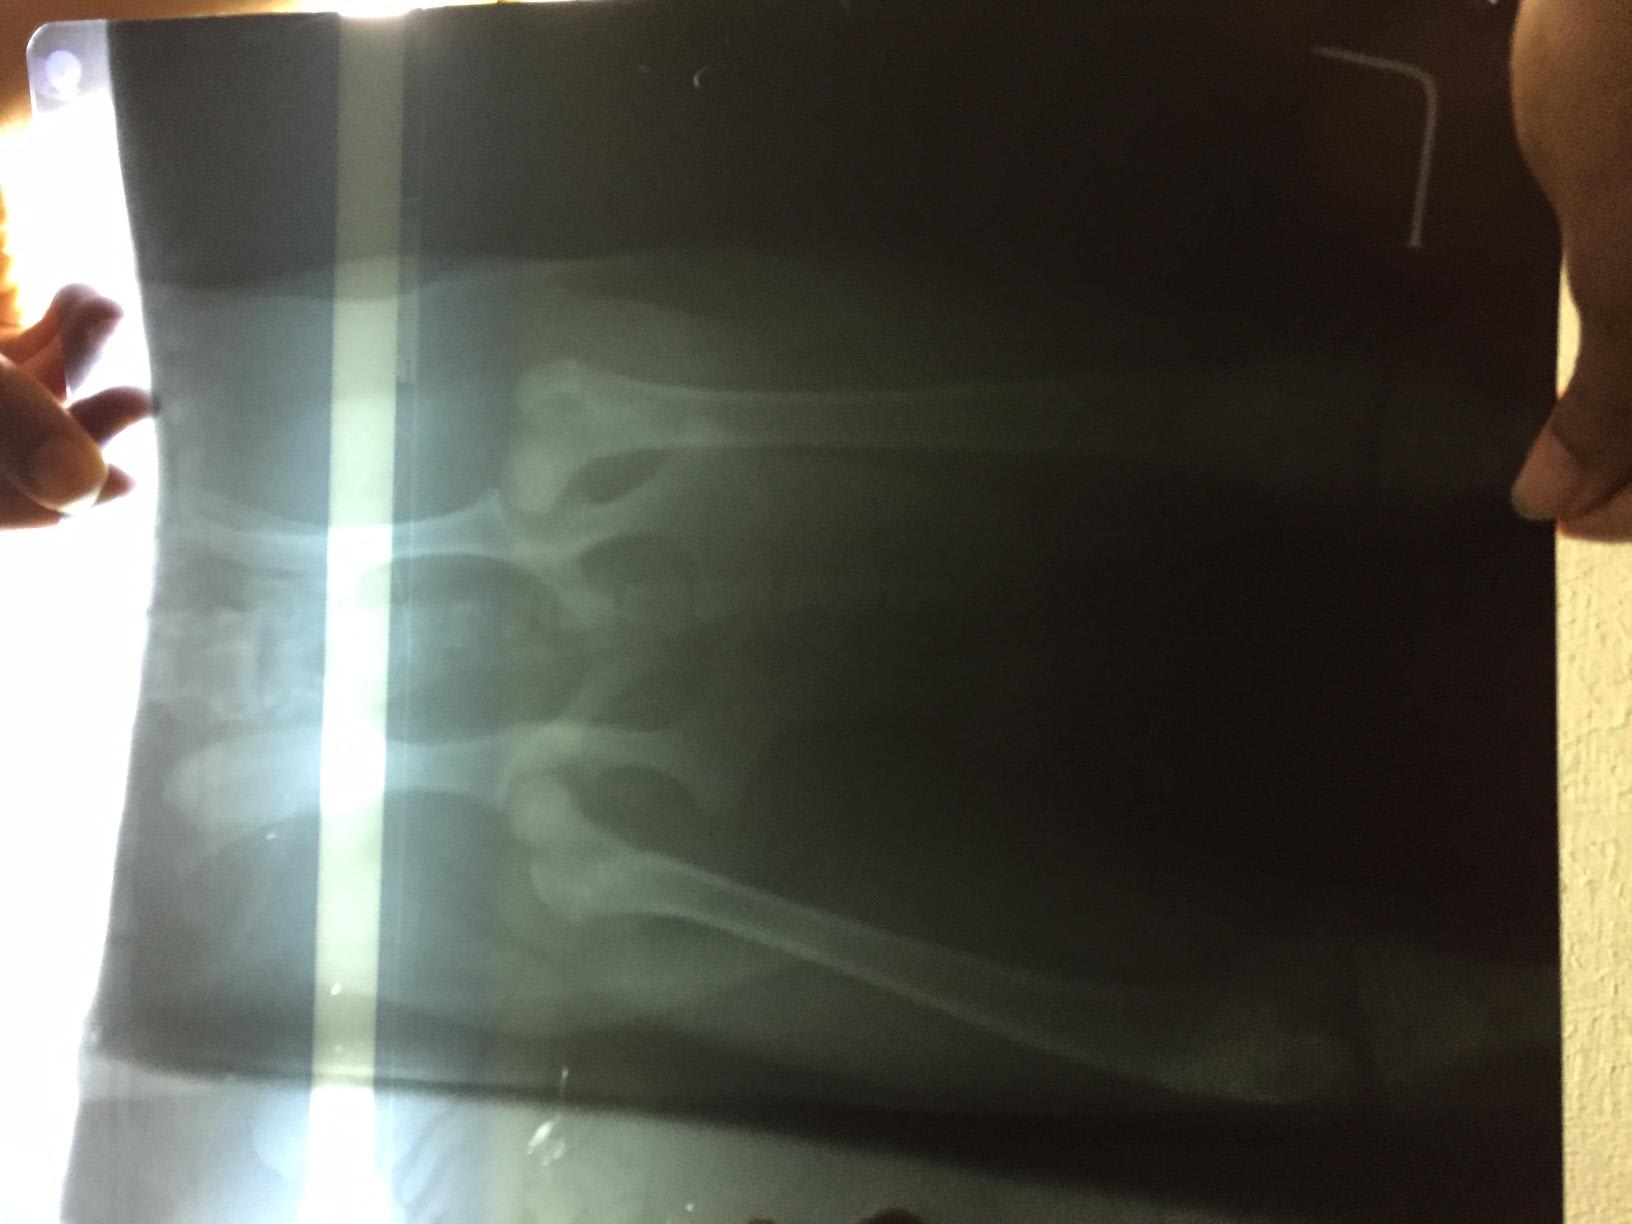

I showed the X-Ray to 2 doctors. One Doctor said that the position of limbs are not good & this issue may be there for life or may be not & the other doctor said that X-Ray hasn't been positioned properly so it looks like joints are sublimated, also he is a pup, so suggested to continue with HD tablets & Pet joint for a month. She also asked me not to overthink until Browny is not able to walk or move. Need one more opinion. Need to understand what does the X-Ray show..

I agree with the doctor who said the x-rays were not positioned properly. In order to obtain really diagnostic quality hip x-rays, the patience should be fully sedated. Without being able to bend the hips all the way downward, you simply can not obtain completely accurate results. Depending on the current clinical picture, I might possible recommend starting medication. Joint supplementation definitely can't hurt, but starting an NSAID at this early of an age is not advisable unless there is clear and obvious discomfort / inflammatory pain. Hope this helps!